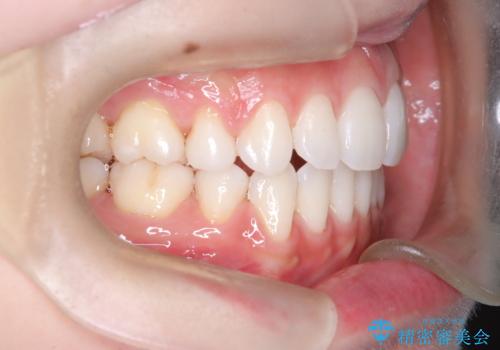

上下左右の小臼歯を抜歯後、ワイヤー矯正装置を装着し、全体のバランスを見ながら歯を移動させていきました。特に前歯の後方移動では、抜歯スペースを活かして口元を内側に下げることに重点を置きました。また、八重歯も時間をかけて丁寧に整列させ、左右の正中(真ん中の位置)もぴったりと揃えることができました。

治療期間は約2年で、歯並びだけでなく横顔の印象も大きく改善されました。治療後には「口元がすっきりして笑顔に自信が持てるようになった」とのお声をいただきました。現在は後戻りを防ぐため、保定装置(リテーナー)を使用しながら経過観察中です。ワイヤー矯正は審美性と機能性を両立できる有効な選択肢の一つです。